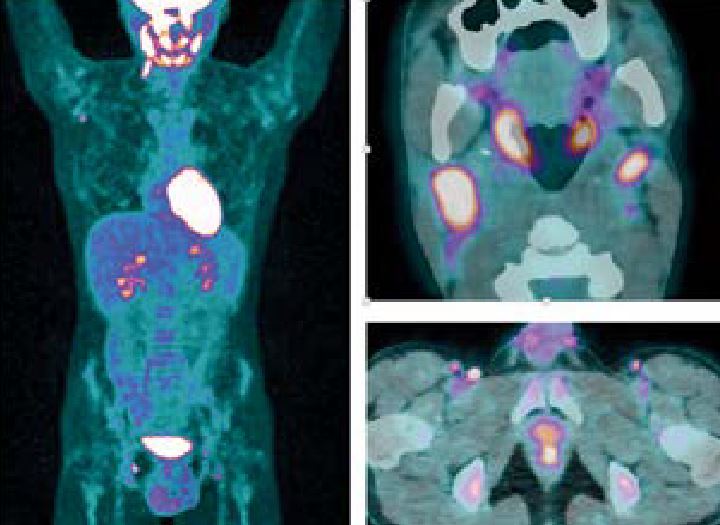

• Oncologie (métastases, tumeurs primitives, réponse au traitement...)

• Par Lutétium 177 dans le cadre du cancer prostatique métastatique

• Par Radium 223, également dans le cancer prostatique métastatique